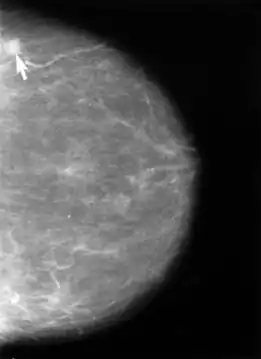

В настоящее время в мире в подавляющем большинстве случаев для диагностики рака женской молочной железы (РМЖ) используют рентгеновскую проекционную маммографию, пленочную (аналоговую) или цифровую. В Европе и странах Северной Америки цифровая маммография на основе детекторов прямого преобразования постепенно вытесняет плёночную из-за наличия больших возможностей по работе с полученным изображением и возможности интеграции с медицинской информационной сетью. Причём в рутинной цифровой рентгенографии применяются детекторы на основе a-Si (аморфного кремния), а в цифровой маммографии детекторы на основе a-Se (аморфного селена) вследствие прямого преобразования сигнала и отсутствия промежуточных этапов в получении рентгеновского изображения у селеновых детекторов. Самыми первыми и самыми старыми аппаратами (с 2000 года) на рынке являются маммографы General Electric (детекторы aSi с разрешением 4 пары линий на мм).

Рентгеновская маммография является золотым стандартом для выявления рака молочной железы, так как обладает самой высокой специфичностью (более 92 %). В развитых странах Европы все женщины старше 45 лет проходят обязательную процедуру рентгеновской маммографии, что позволило значительно снизить смертность от рака молочной железы. В России обязательным является регулярное обследование женщин старше 40 лет.